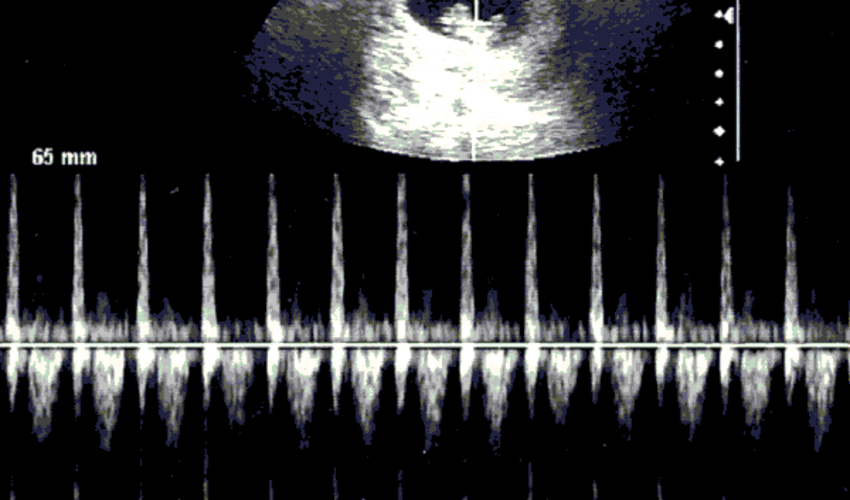

Bebek kalp atışı resmi

Bebeğinin kalp atışları ultrasonda aşağıdaki gibi görünebilir.